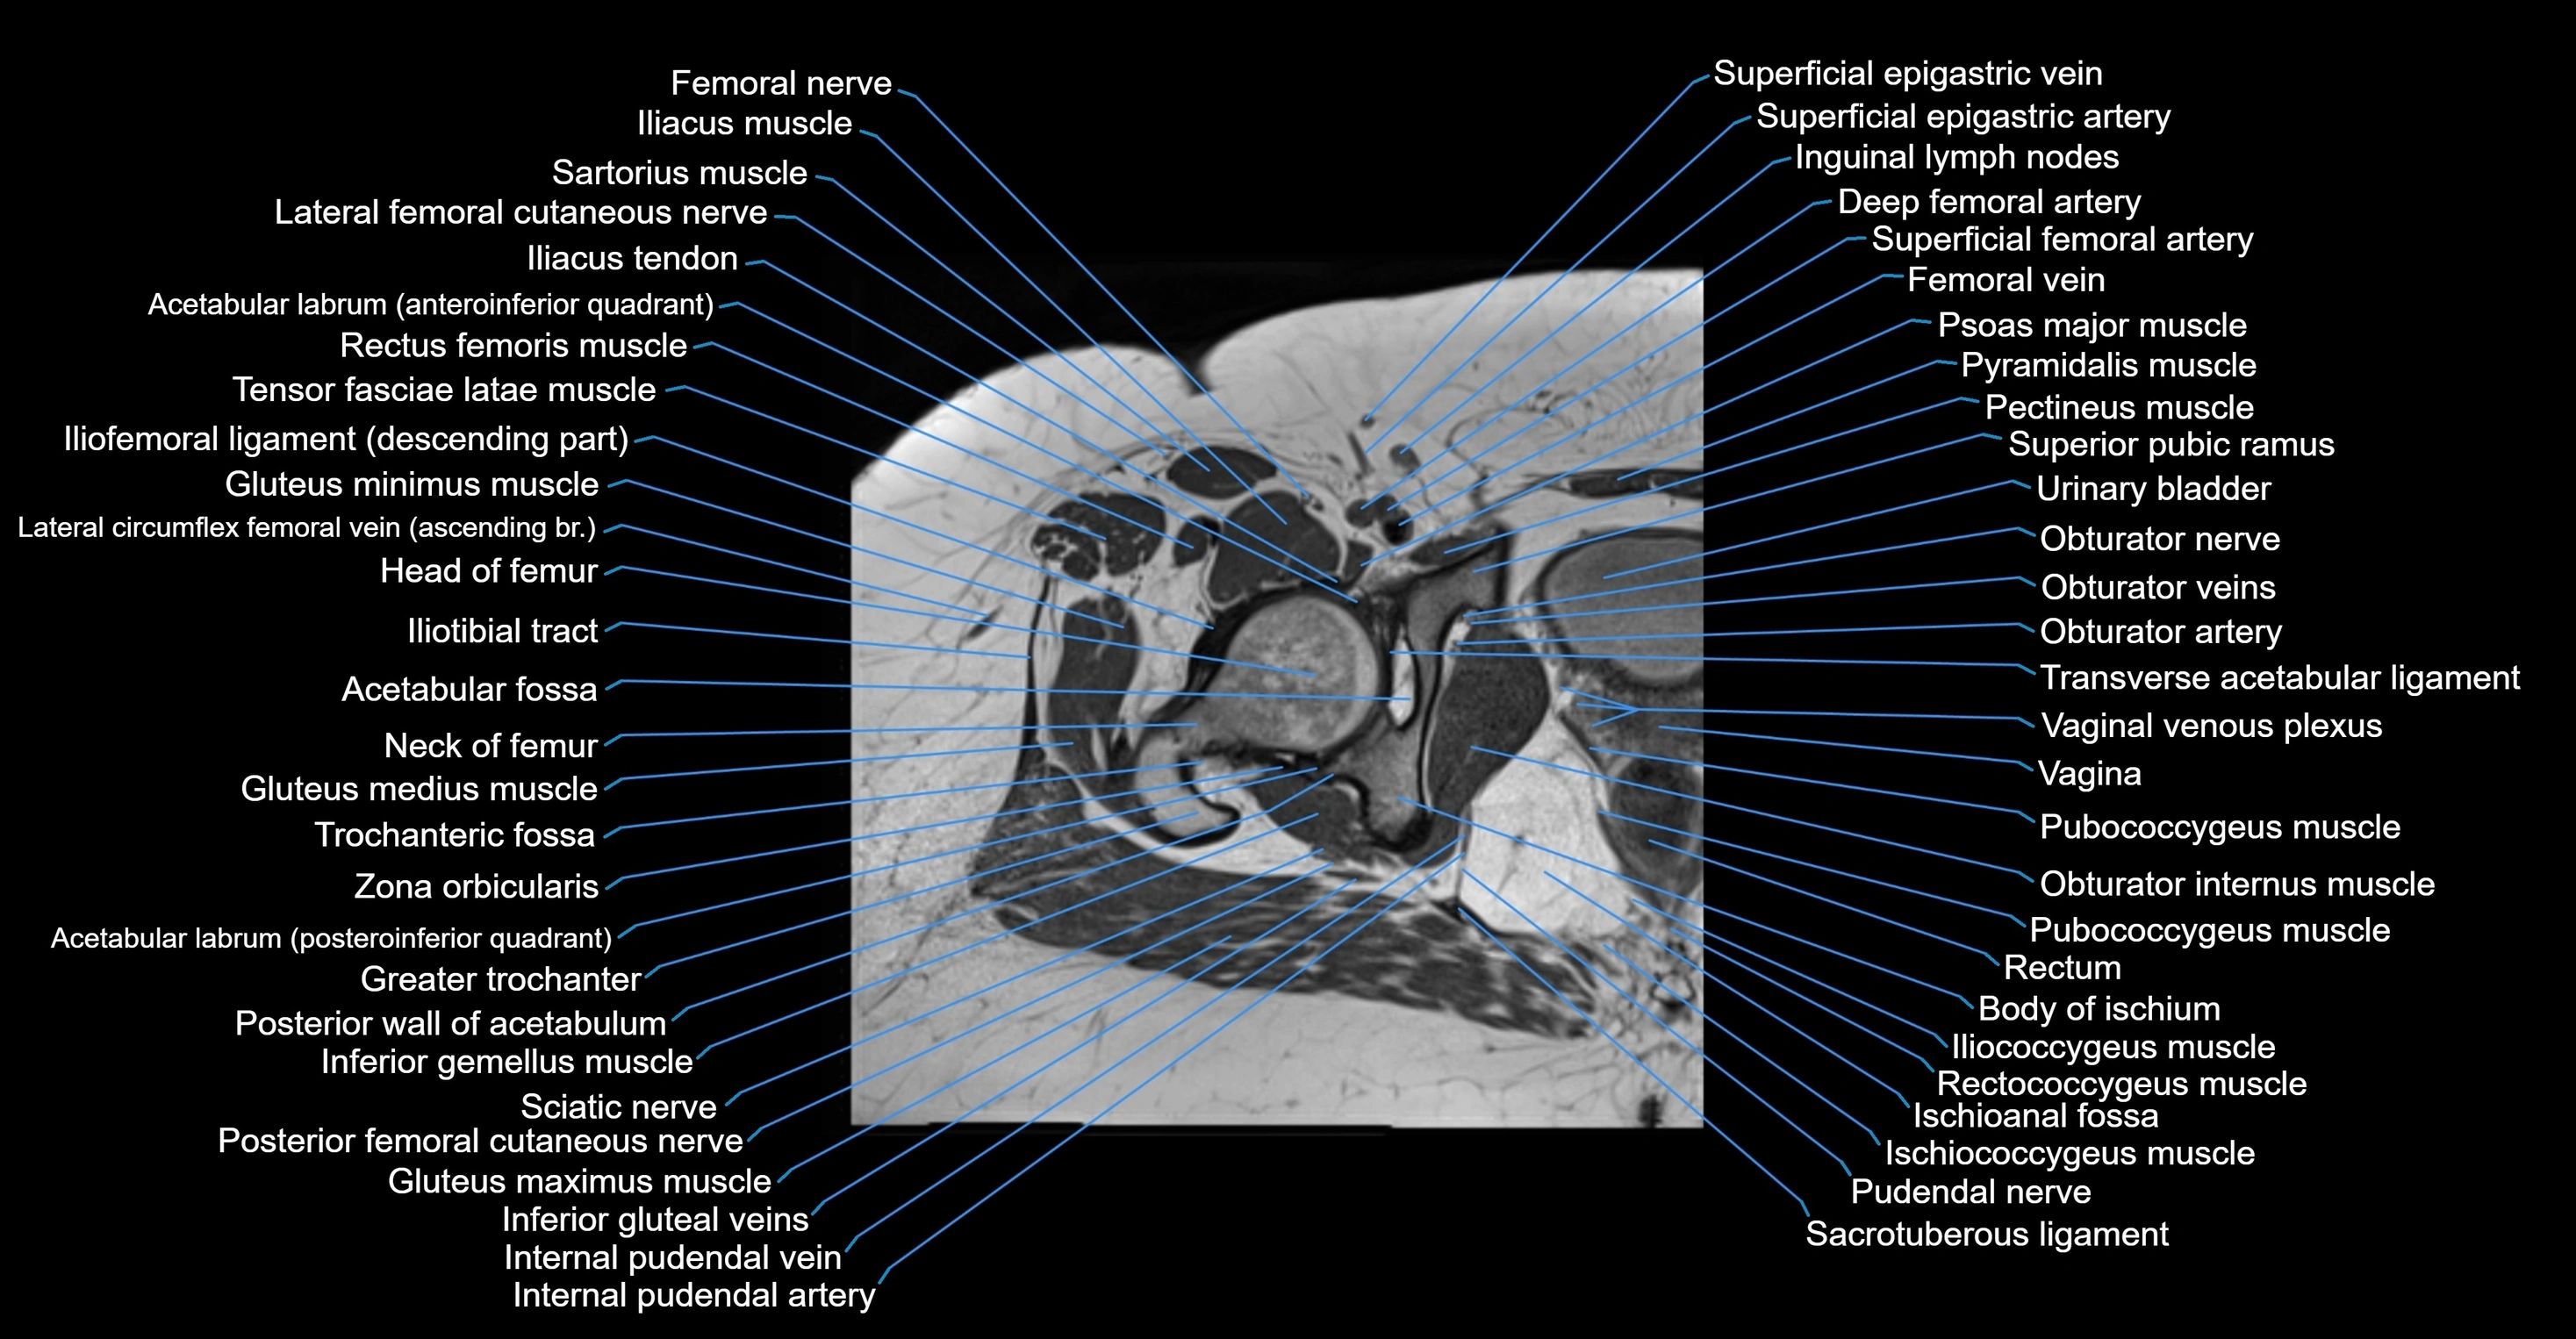

- Acetabular labrum

- Gluteus maximus muscle

- Gluteus medius muscle

- Gluteus minimus muscle

- Greater trochanter

- Head of femur

- Iliococcygeus muscle

- Iliofemoral ligament

- Iliotibial tract

- Inferior gemellus muscle

- Ischioanal fossa

- Ischiococcygeus muscle

- Obturator internus muscle

- Obturator nerve

- Obturator vein

- Obturator veins

- Posterior femoral cutaneous nerve

- Pubococcygeus muscle

- Pudendal nerve

- Rectum

- Sacrotuberous ligament

- Transverse acetabular ligament

- Urinary bladder

- Vagina

- Vaginal venous plexus